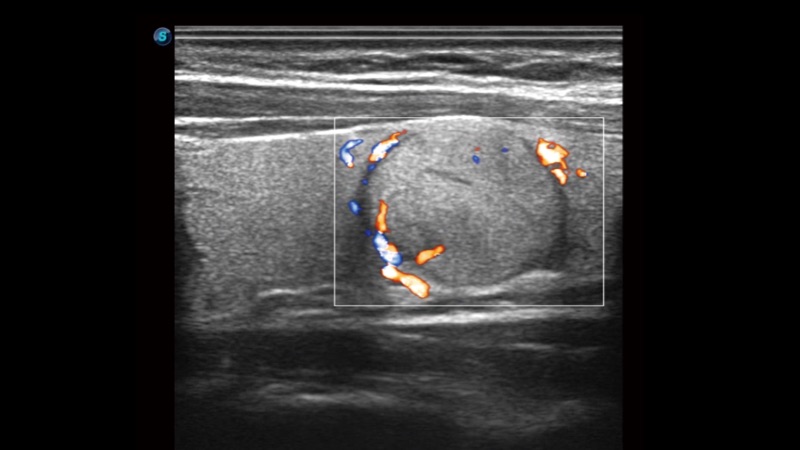

凭借狗万官方网站先进的成像技术和优异的探头技术提供的清晰的图像表现,您可以更自信地做出临床决策。